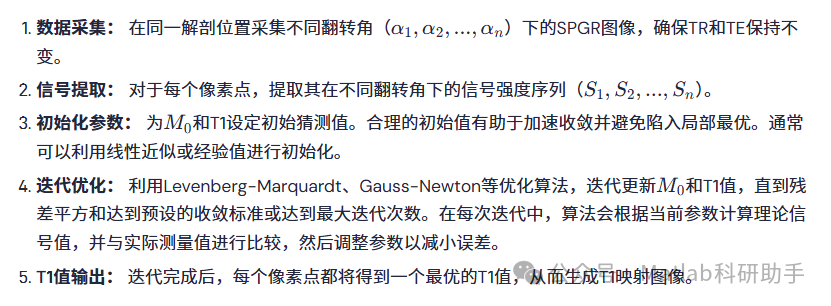

NLLS算法的实施步骤通常包括:

⛳️ 运行结果